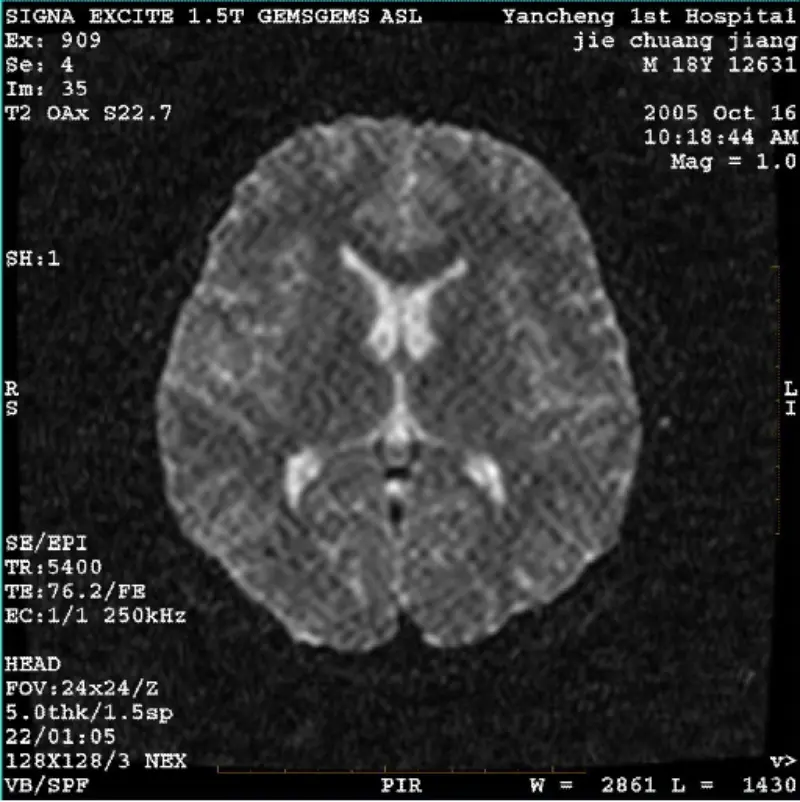

Baca LagiSISTEM: 1.5T Signa Twin Excite II (Versi Perisian 11.0M4) MASALAH/SIMPTO DWI (mod Zum dan mod keseluruhan) dan fiesta (mod zum dan mod keseluruhan) mempunyai imej artifak reticulate atau corduroy yang boleh dilihat tidak kira apabila menggunakan gegelung badan atau kepala gegelung, imej rutin......